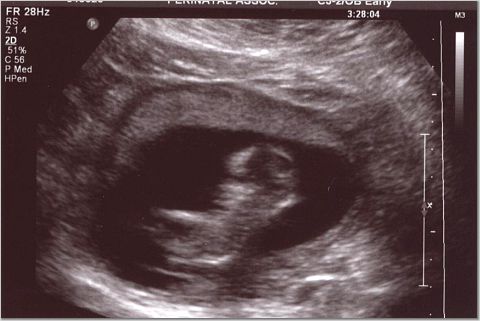

I got to watch TV with my baby as the star!!! Everything looked good and we'll have partial results on Monday. The genetic counselor really freaked us out a biut, prior to the sono. DH actually asked her to do the sono first then talk to us about what could be wrong after..he was getting really worried. But so far everything looked great, we got some pics and we scheduled our level 2 for July 12...it'll be a nice 30th b-day gift!!

Oh and the heartbeat was 178...tech told me old wives tale was higher girl..so we'll see..not buying pink yet though!! Image Attachment(s):